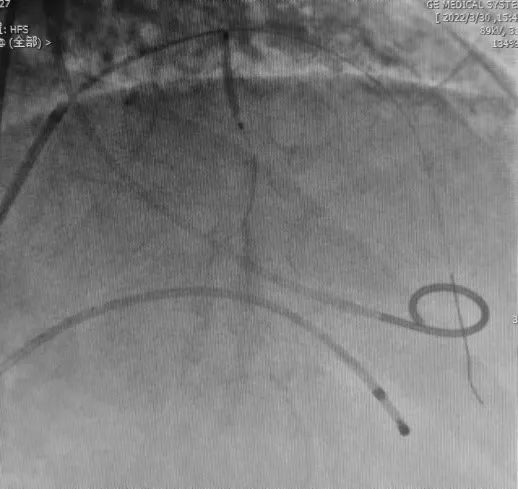

术前

将OWT球囊放置在间隔支近段,打起球囊后封堵住间隔支口部,用2ml造影剂确认目标间隔支,造影剂无反流,确认对比剂到达目标区域,将无水酒精注射至间隔支。